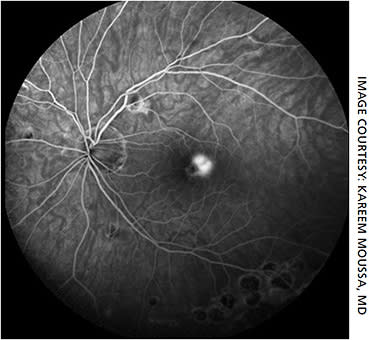

Pathology in the macula is most accessible to imaging by OCT-A. Take the example of a 39-year-old woman with multifocal choroiditis who presented with metamorphopsia in the left eye. SD-OCT showed disruption of the outer retinal structures and accumulation of abnormal material (Figure 2). Meanwhile, OCT-A revealed an abnormal network of vessels in the outer retina and choriocapillaris (Figure 4), consistent with neovascularization. OCT-A in this case localizes the neovascularization to the outer retina and choriocapillaris.